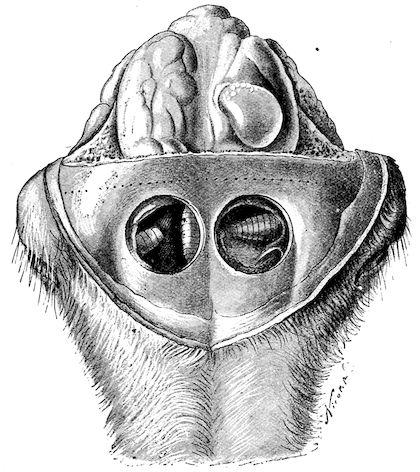

Fig. 8.—Transverse section through the middle region of the face in a pig suffering from osseous cachexia.

18In the final stages, the bones may be cut with a knife, and a time arrives when bony tissue seems completely to have disappeared; thus, as shown in Fig. 8 herewith, it was possible to cut the entire head of a pig into thin slices without the slightest difficulty. All parts of the head had been affected by the softening change.